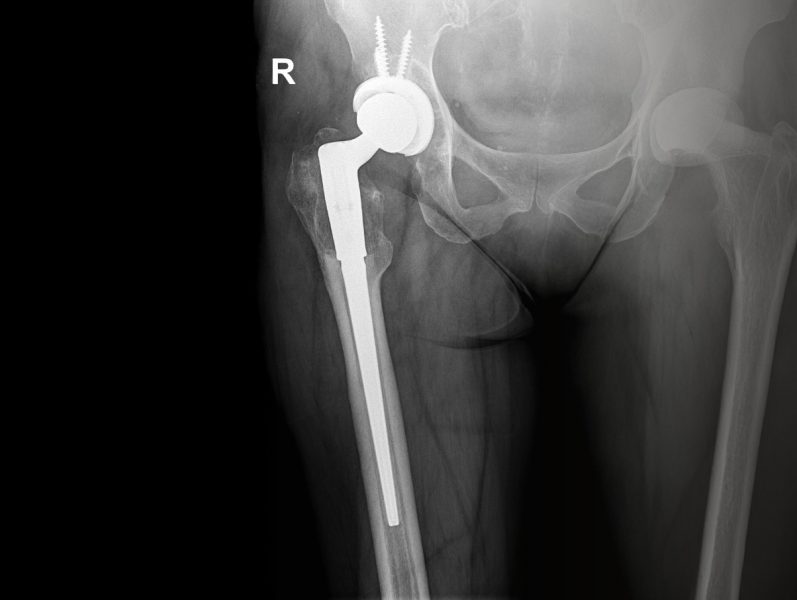

In unserer Abteilung werden primäre und Revisionsendoprothesen an Hüft –, Knie – und Schultergelenken durchgeführt.